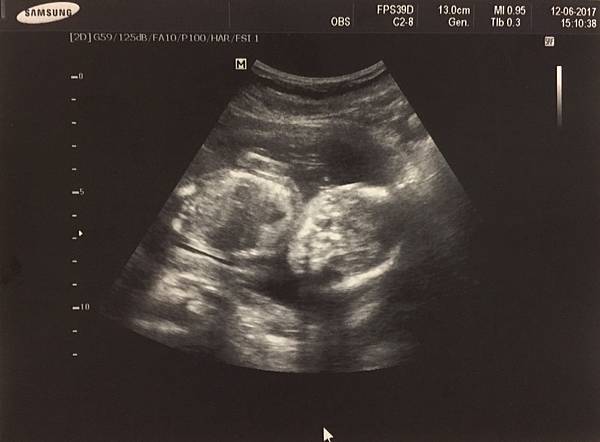

20週超音波

其實連續三次醫師都說應該是女娃了

但我一直覺得可能會翻盤,所以就是半信半疑

董醫師照超音波非常細心,會告訴你這是哪裡哪裡

還有數手指頭,反而是我常常聽到放空(這位媽媽這樣對嗎)

看到小寶貝的小手小腳覺得天啊太可愛了![]()